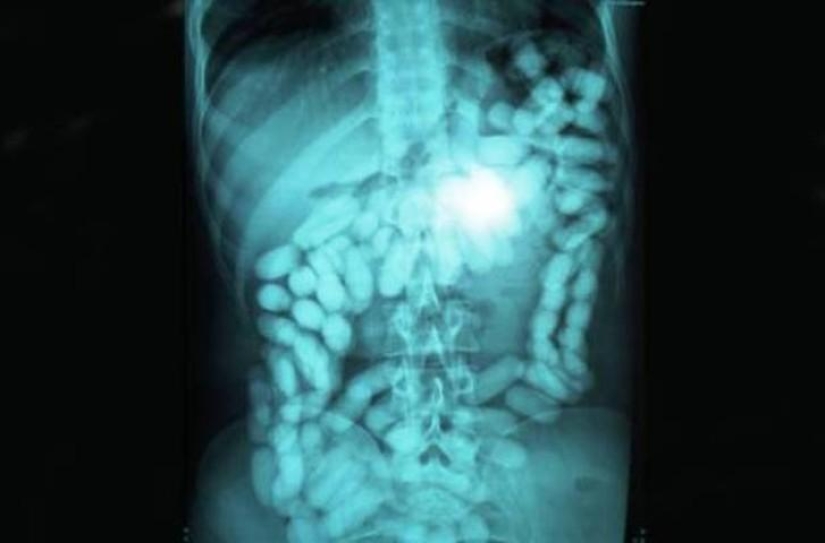

10. The nail.

12. Cutlery.